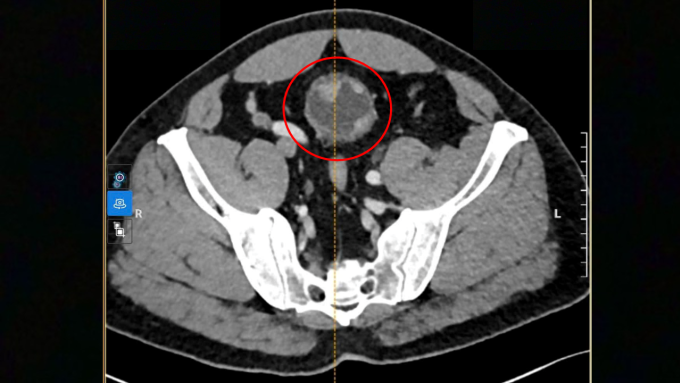

Ảnh CT ghi nhận khối u to bất thường xâm lấn cơ bàng quang người bệnh. Ảnh: Bệnh viện Đa khoa Tâm Anh

Khối u ác tính đường kính 4-6 cm có dấu hiệu xâm lấn vào lớp cơ bàng quang bệnh nhân. Êkíp TS.BS Nguyễn Hoàng Đức, Trưởng khoa Tiết niệu, Trung tâm Tiết niệu – Thận học – Nam khoa, Bệnh viện Đa khoa Tâm Anh TP HCM, quyết định phẫu thuật “2 trong 1” mục tiêu cắt bỏ toàn bộ bàng quang triệt căn khối u và tạo hình bàng quang mới từ ruột non cho người bệnh bằng robot Da Vinci Xi.